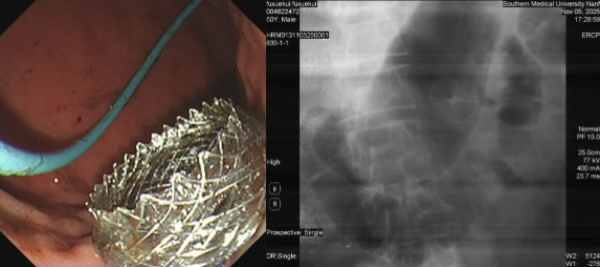

为创造安全的手术条件,手术前,医疗团队用了一个半小时进行了极其细致的洗胃和胃内食物残渣清理工作。随后的EUS-GE操作仅用时十余分钟,在超声胃镜与X线的精准引导下,团队成功经胃体实施了胃空肠吻合支架植入,巧妙绕开了肿瘤梗阻区域,手术取得圆满成功。